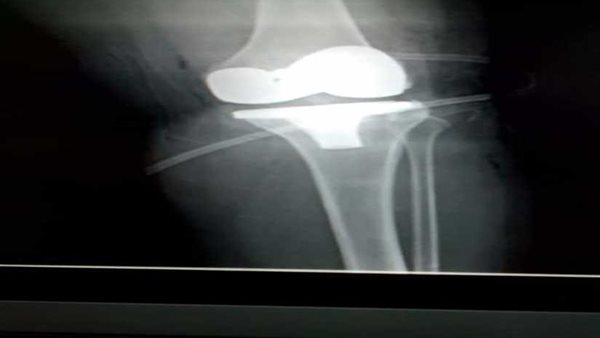

وأوضح ناجى أن العملية تمت بقرار علي نفقة الدولة (ضمن منظومة إنهاء قوائم الإنتظار) بدون تحميل المريضة أي اعباء مالية، حيث تم تركيب مفصل ركبة صناعي من مادة التيتانيوم، حيت كانت فى حالة تآكل وتيبس مفاصل الركبة (ال خشونة)